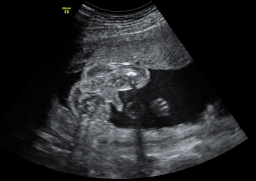

En la semana 20 de gestación, la ecografía en 2D muestra los genitales de un feto varón ya formados, aunque los testículos aún se encuentran alojados dentro de la cavidad abdominal. En unas semanas descenderán hasta las bolsas escrotales.

Imagen de los genitales de un niño en 2D